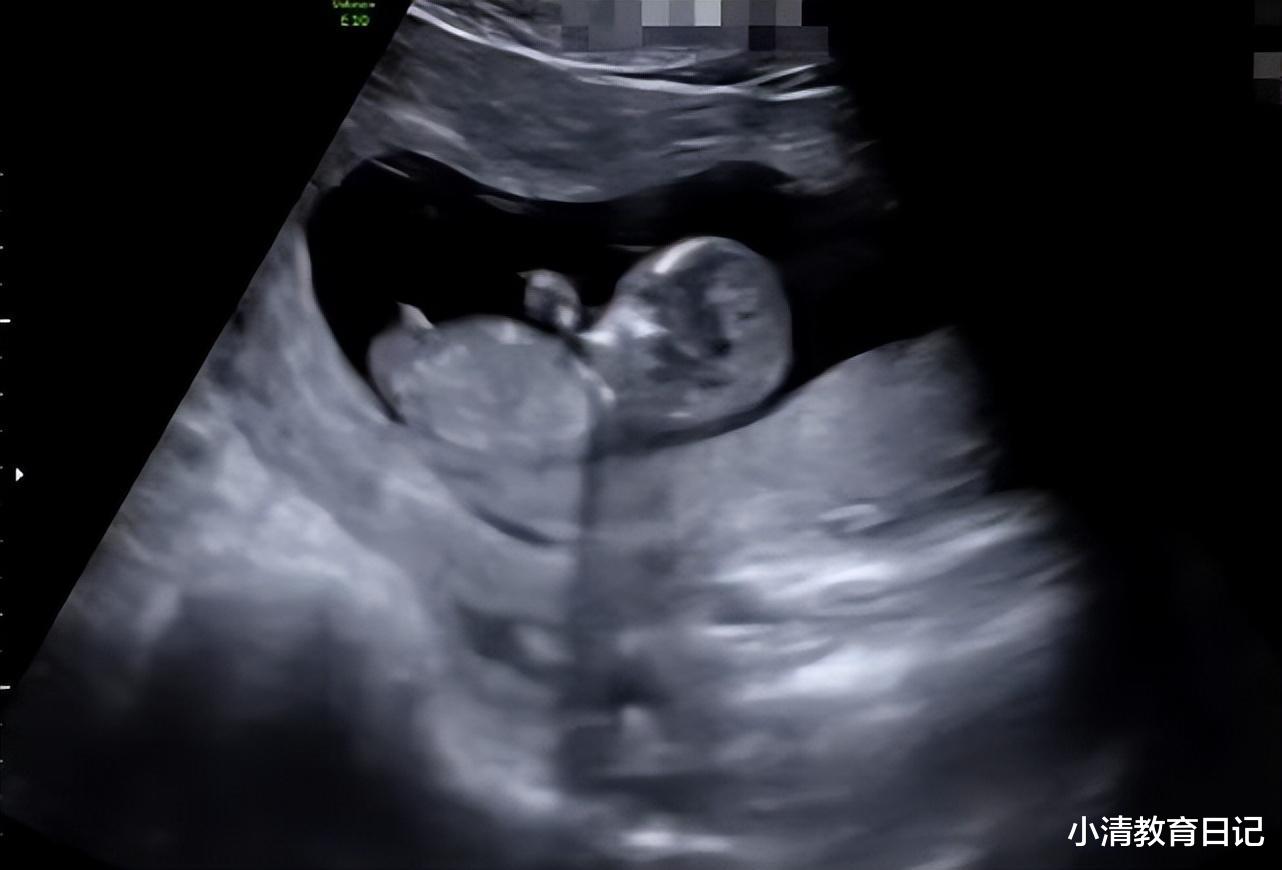

与此同时 , Selina还首次公开了宝宝B超照 , 小宝宝躺在妈妈肚子里 , 十分可爱 。 而为了当好新手妈妈 , Selina也有认真学习和记录 , 超有爱 。

而对于Selina晒出的宝宝B超照 , 网友看后纷纷表示她怀的是个男孩 , 因为有相关特征被曝光 。